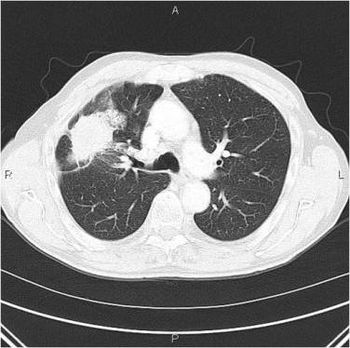

A 31-year-old male, recently on active duty in the military, presents to the ER with approximately one- week history of abdominal bloating, early satiety, and back pain. The patient has recently returned from overseas duty in Iraq, but otherwise has had no other significant travel history. On specific questioning, the patient reports he has “probably been exposed to toxic chemicals.” The patient is otherwise in healthy condition, and denies recent surgery, or illness, and takes no medication. He admits to social alcohol use only, and denies IV drug abuse.